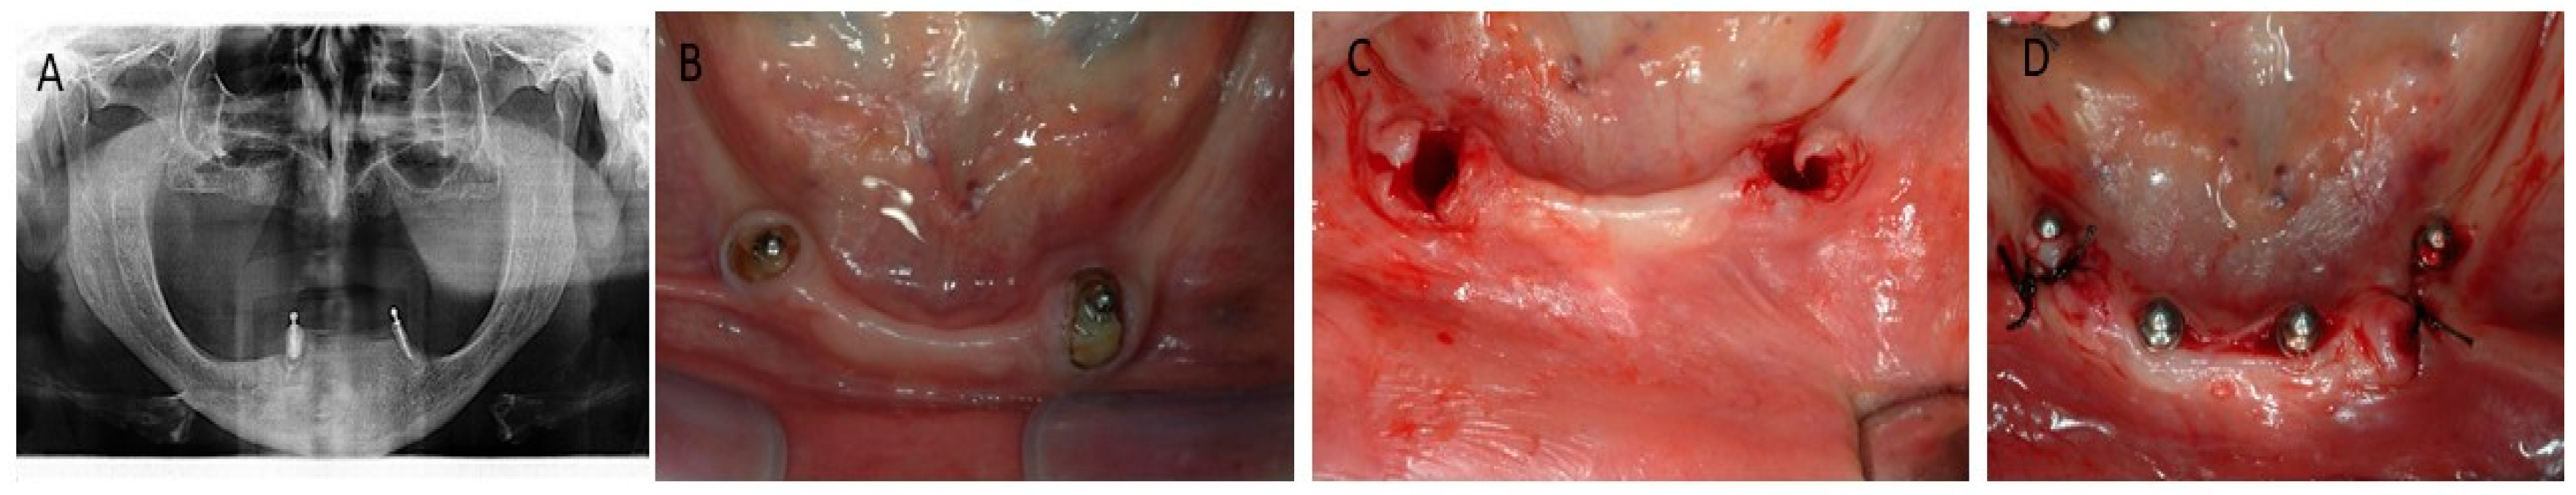

2.3. Surgical Procedure